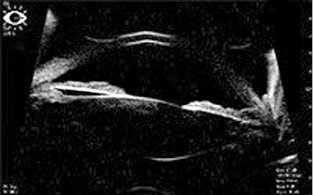

По данным ультразвуковой биомикроскопии переднего отрезка глаза (правый глаз — рис. 1, левый глаз — рис. 2), на обоих глазах отмечены выраженный пролапс радужки у корня, патологический контакт пигментного листка радужной оболочки с передней поверхностью хрусталика и цинновыми связками, размеры хрусталиков обоих глаз 3,62 мм, глубина передней камеры 3,96 мм.

Рис. 1. Правый глаз, исходная ультразвуковая биомикроскопия

Рис. 2. Левый глаз, исходная ультразвуковая биомикроскопия